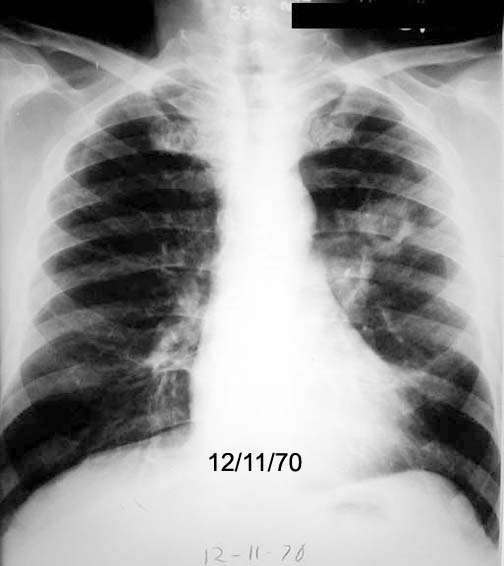

Case 1 Labeled Image What are the conditions where you get thin walled cavities?